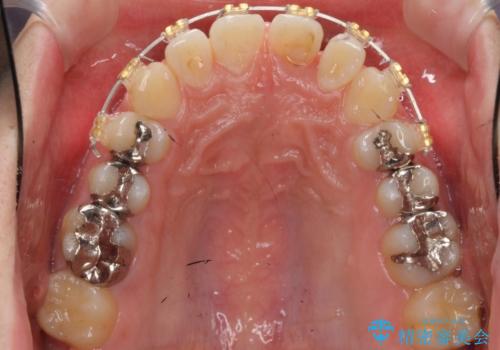

- 矯正装置

- 審美装置

- 治療期間

- 4ヶ月

- 前歯のねじれを部分矯正で治療しました。

奥歯のかみ合わせを変えずに、費用を抑えて短期間に治療したい方におすすめです。

奥歯のかみあわせも問題なく、また、下の前歯のがたつきが元からない場合は上の部分矯正が十分可能です。